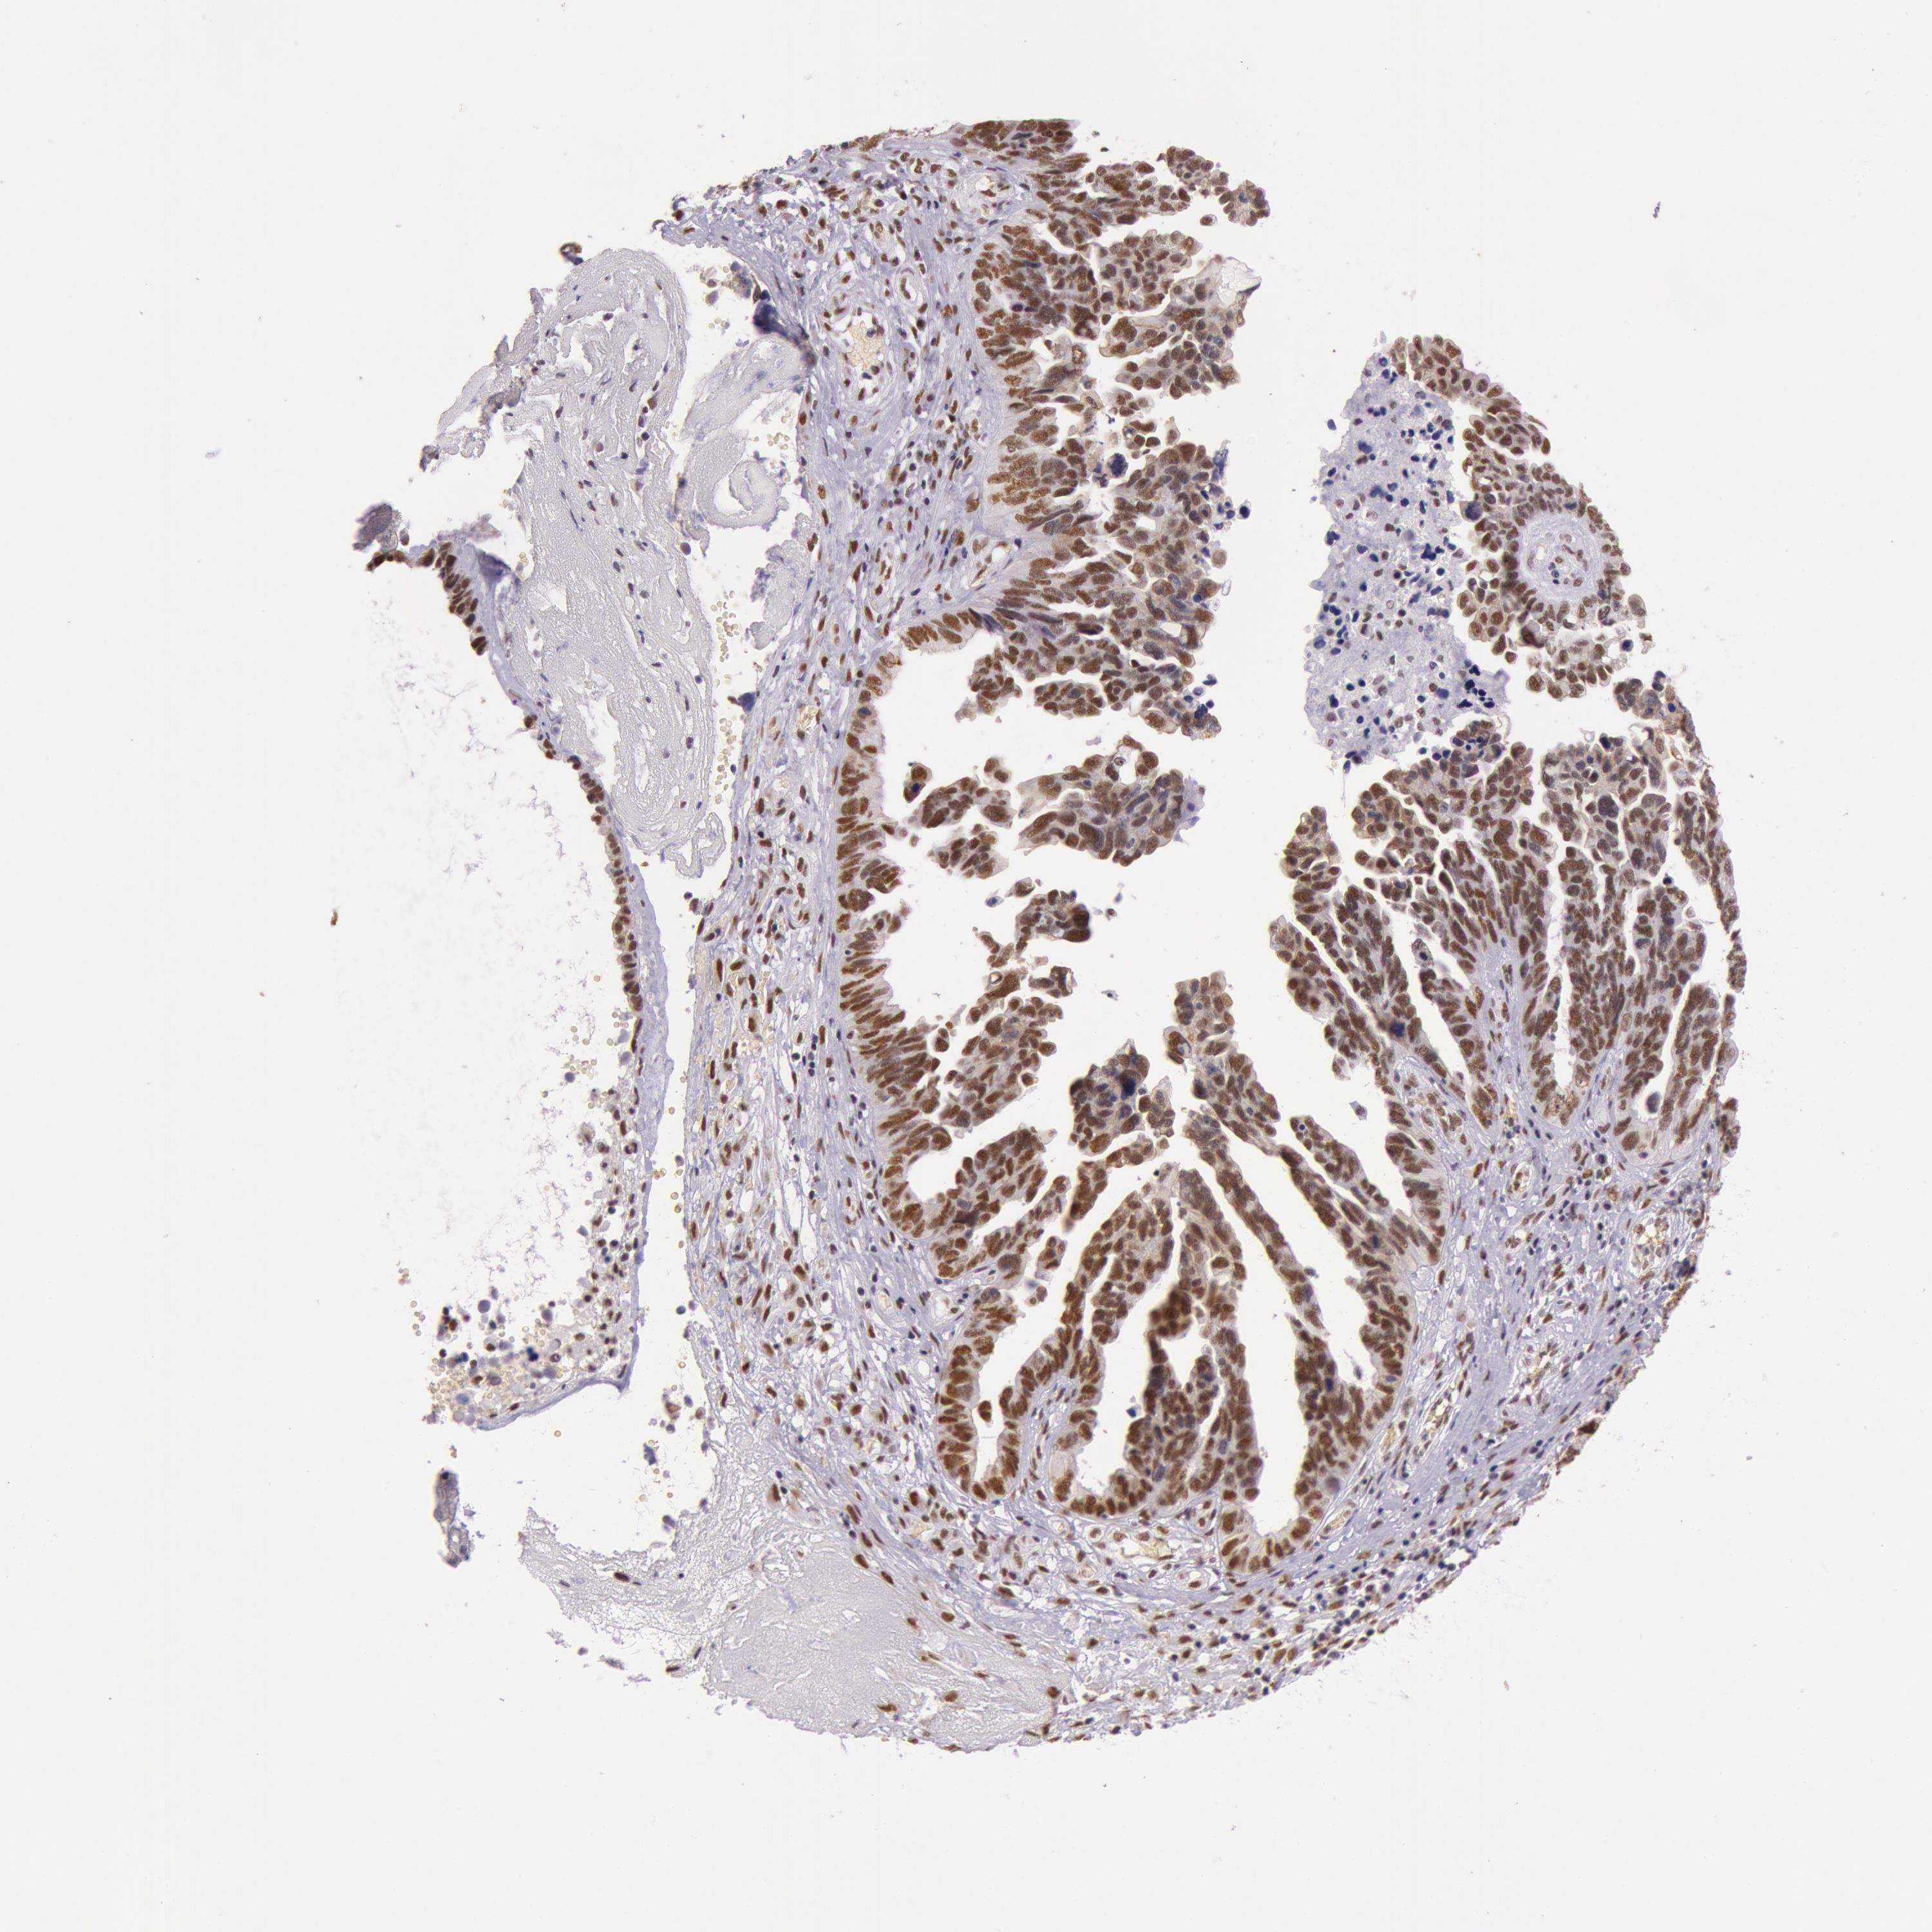

OVARIAN CANCER - Protein expressioni

A mouse-over function shows sample information and annotation data. Click on an image to view it in a full screen mode. Samples can be filtered based on level of antibody staining by selecting one or several of the following categories: high, medium, low and not detected. The assay and annotation is described here.

Note that samples used for immunohistochemistry by the Human Protein Atlas do not correspond to samples in the TCGA dataset.

Antibody stainingi

Antibody staining in the annotated cell types in the current human tissue is reported as not detected, low, medium, or high, based on conventional immunohistochemistry profiling in selected tissues. This score is based on the combination of the staining intensity and fraction of stained cells.

Each image is clickable and will lead to virtual microscopy that enables deeper exploration of all samples and also displays staining intensity scores, fraction scores and subcellular localization as well as patient and tissue information for each sample.

Antibody HPA001429

Staining

High

Medium

Low

Not detected

Intensity

Strong

Moderate

Weak

Negative

Quantity

>75%

75%-25%

<25%

None

Location

Nuclear

Cytoplasmic/membranous

Cytoplasmic/membranous,nuclear

Carcinoma, endometroid

Cystadenocarcinoma, serous, NOS

Cystadenocarcinoma, mucinous, NOS